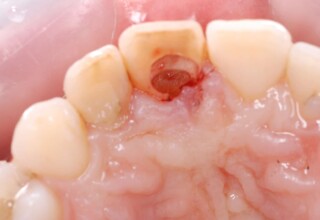

A rare case of dark root canal teeth with additional external absorption on the central incisor. After removal of the affected tissues of the central incisor, the tooth could not be directly bleached because of the soft tissue contact. The tooth was initially restored to provide the original tooth form, then it was bleached and the restoration was finalized.

Initial appearance

Final appearance